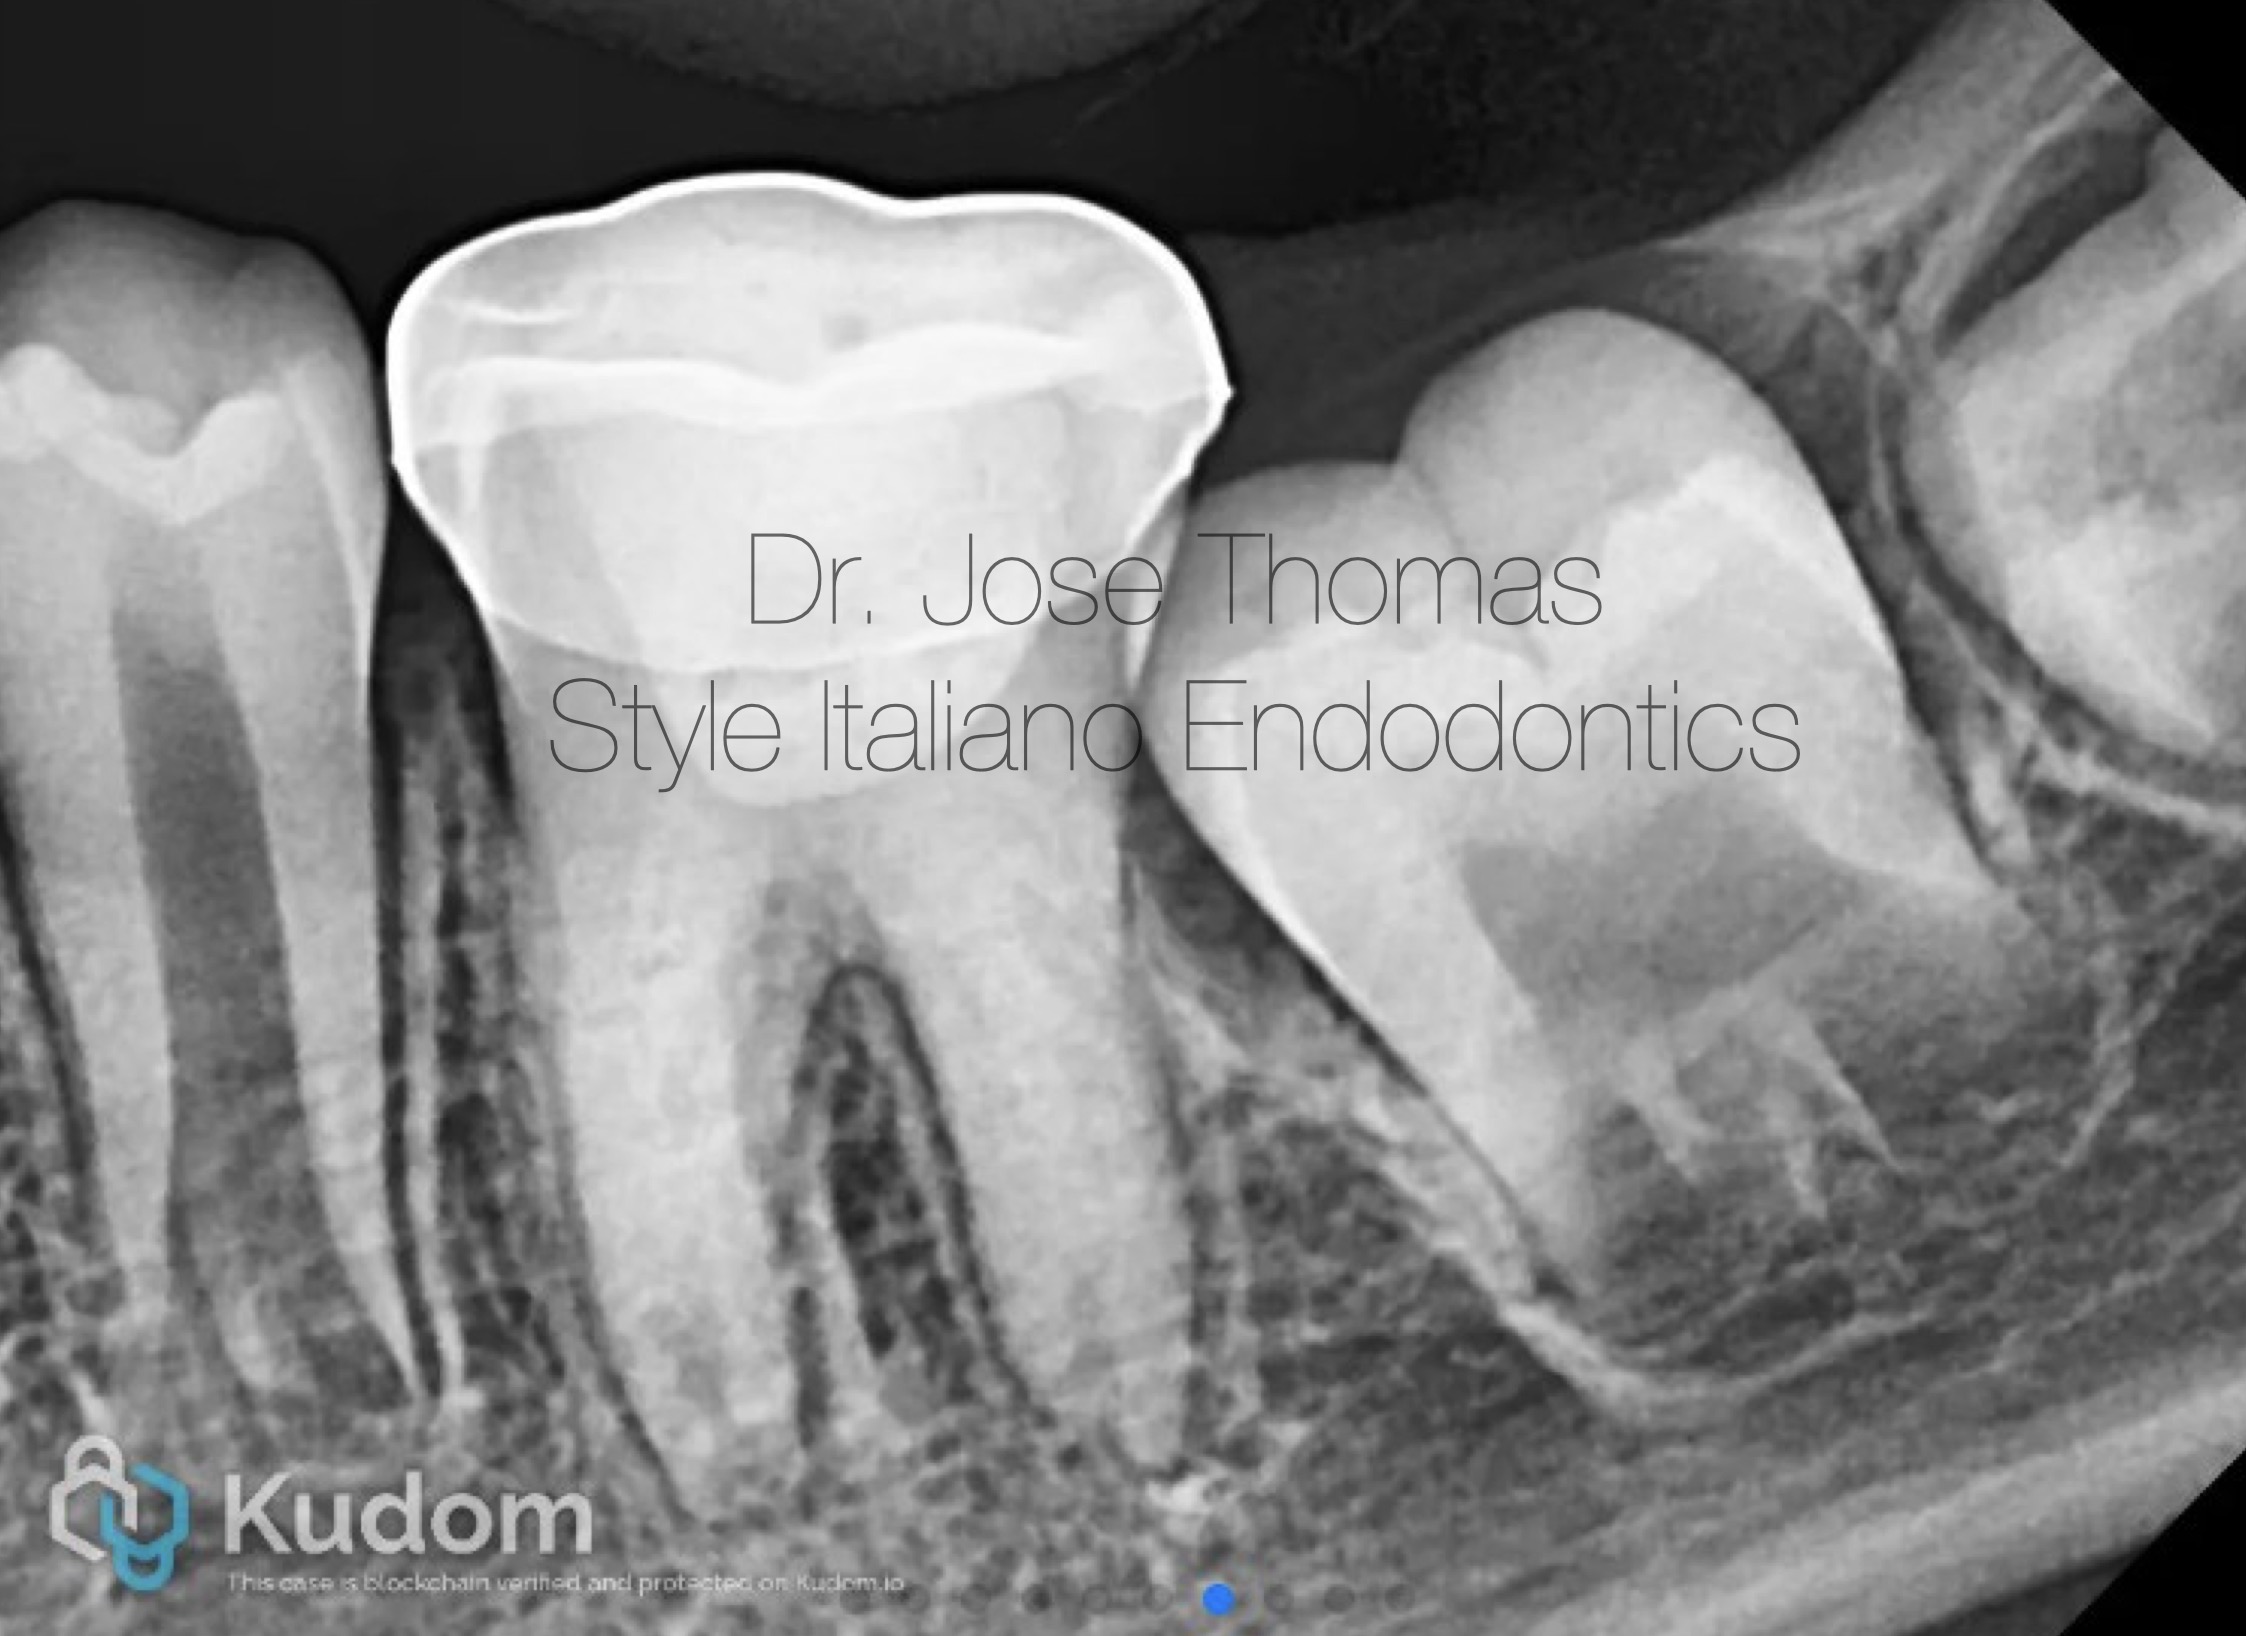

Fig. 3

The canals and chamber were then thoroughly dried with paper points and Biodentine® (Septodont, Saint-Maur-des-Fossés, France) was placed into the canals and up to the working length in small increments and gently condensed with a hand plugger. A resin modified GIC liner was used to close off the canal orifices, followed by restoration of coronal seal with composite build-up. Radiograph of 36 showing Biodentine® in canals and access closed with composite.